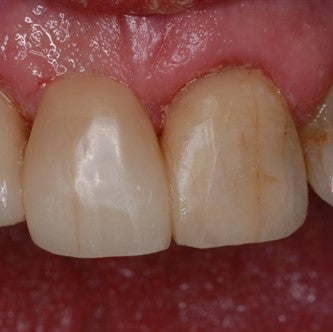

Direct composite veneers #'s 8 & 9

Introduction: #'s 8 & 9 have incisal wear and are lingually inclined. Perfect for no prep veneers. Patient chose direct composite over porcelain due to cost. Before Before... Read More